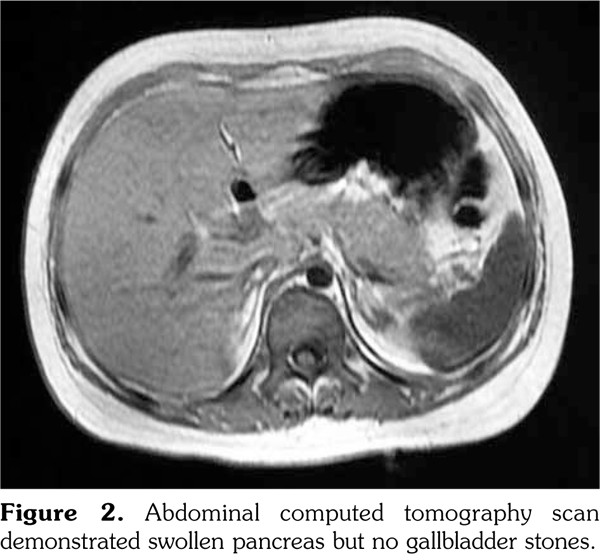

An 11-year-old girl was admitted to our department with a six-month history of anorexia and rashes on her face and extremities (Figure 1). On admission, her axillary temperature was 37.7°C, heart rate was 130 beats/minute, blood pressure was 82/47 mmHg, respiratory rate was 22 breaths/minute, and oxygen saturation was 95%. Cardiac examination revealed a soft systolic murmur at the apex with low heart sounds. She had malar rash, discoid rash, hepatosplenomegaly, and edema of the lower extremities. The subsequent autoimmune and serologic workup came back positive for anti- nuclear antibody at a titer of 1:3200, positive anti- double stranded deoxyribonucleic acid, anti-Smith antibody, and low complements (0.28 g/L) and complement 4 (C4) (0.03 g/L). Other laboratory studies exhibited anemia (red blood cell 3.1∞1012/L, hemoglobin 99 g/L), proteinuria (24-hour urine protein 300 mg/day), elevation of acute-phase reactants (C-reactive protein 132 mg/L, erythrocyte sedimentation rate 54 mm/hour), hyperamylasemia (208 units/L), hyperlipasemia (1556 units/L), and raised creatine kinase (CK, 375 units/L) and CK-MB (83 units/L). Electrocardiogram revealed sinus tachycardia with T wave inversion. Echocardiography showed normal left ventricular size but global hypokinesia with an ejection fraction of 37%. Abdominal computed tomography demonstrated swollen pancreas but no gallbladder stones (Figure 2). Renal biopsy revealed diffuse proliferative glomerulonephritis Class IV-G. Our patient was diagnosed as having systemic lupus erythematous (SLE) complicated by pancreatitis and myocarditis. SLE disease activity index score was 24. She was treated with a course of pulse methylprednisolone 10 mg/kg/day for three days and subsequently converted to oral prednisone (60 mg/day). In addition, several symptomatic treatments such as bowel rest, nutritional support, somatostatin, and fructose-1,6-diphosphate were also adopted. One month later, intravenous cyclophosphamide 500 mg/m(2) was given. Two months later, repeated echocardiography showed a marked improvement in ejection fraction, abdominal computed tomography revealed a less swollen pancreas, and SLE disease activity index score was 2. The patient was discharged with normal pancreatic (amylase 109 units/L, lipase 285 units/L) and myocardial enzymes (CK 29 units/L, CK-MB 11 units/L).